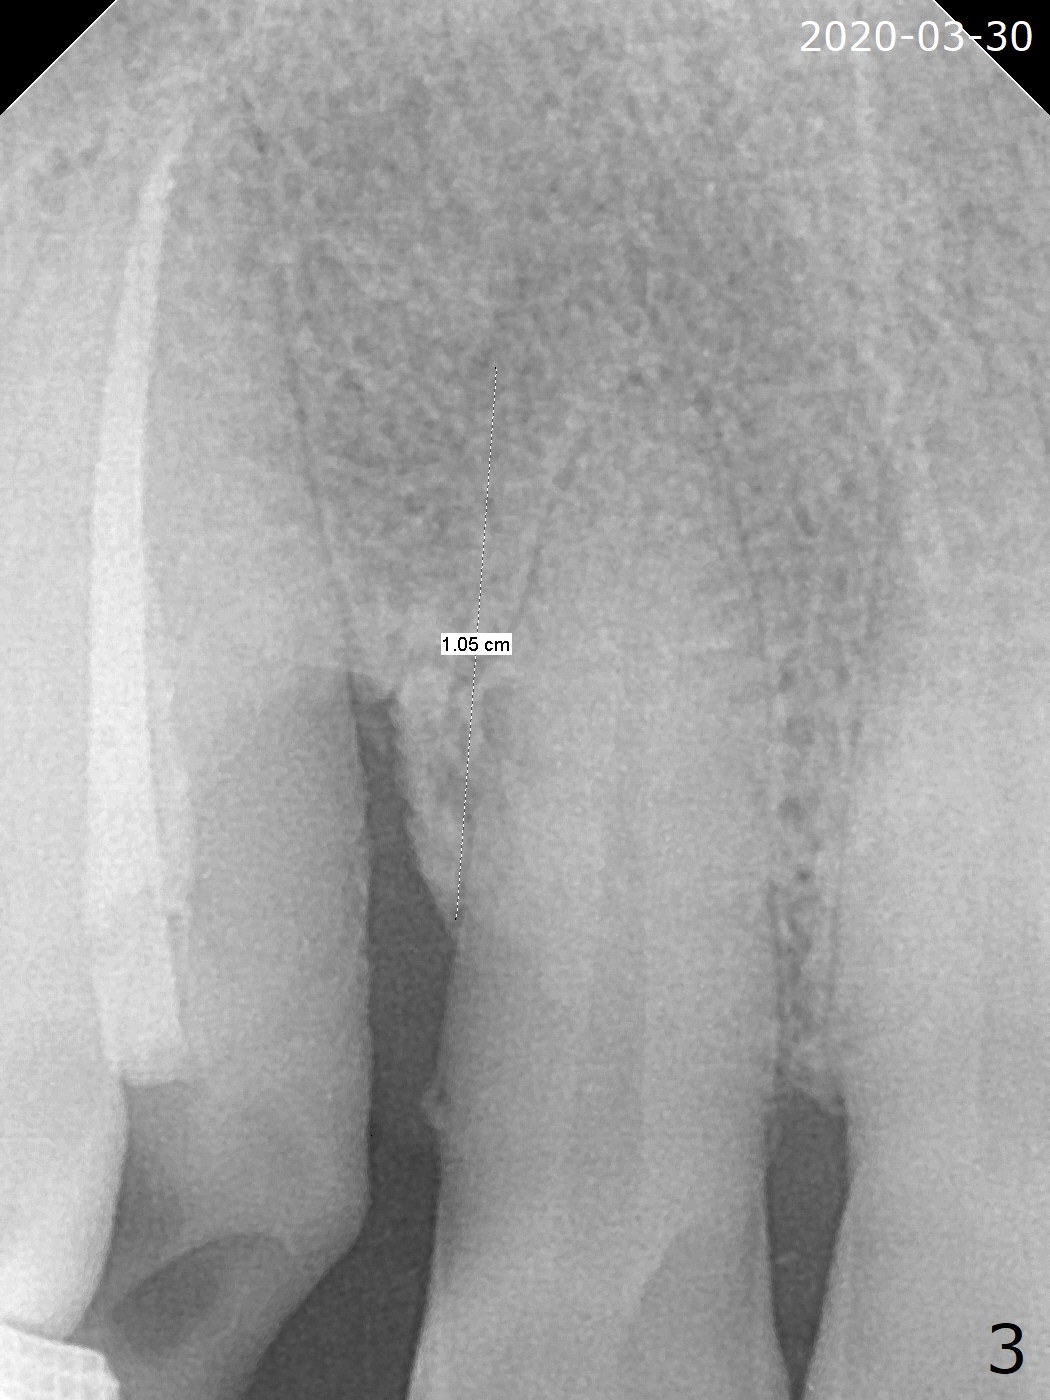

A 62-year-old man had traumatic root fracture at #6 in his teen. The tooth remained asymptomatic until his fifties. Following root canal therapy (Fig.1), the tooth is orthodontically extruded (~ 5 years, Fig.2 (*: bracket)) with apparent disappearance of the infection. The bone distal to #7 seems to increase in height (Fig.3, as compared to Fig.1) and in density (Fig.4). Bone graft could be placed for regeneration with PRF or GEM21S (Fig.5 red (between #6 and 7), pink (buccal to #7 or coronal to the fracture line) circles). With extrusion, the oblique fracture line is more than half or two third supragingival (Fig.6). In spite of severe bone loss, exostosis is present (Fig.7 (mesiobuccal view) E) so that bone graft could be placed palatal to it (Fig.8 red). In case the tooth is non-salvageable, immediate implant will be placed with guide (Fig.9,10). Move lingual button as apical as possible (Fig.12) and make occlusal clearance. Continue extrusion until all of the crack is exposed without deep pocket.